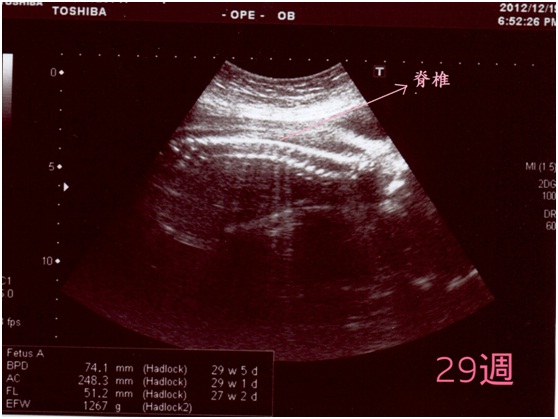

這次產檢,一切正常,大小也比同時期的阿妞大一點點,既然第二胎也註定要剖腹了,我其實不介意她大一點,不然像阿妞出生雖然有2970 公克,但要出院時脫水後只剩2600g,真的好小一隻哦。

這次的超音波照片,非常的lucky的拿到一張非常清楚的側面照,看著這張照片,我有一種覺得我的夢要成真的感覺耶,其實在性別揭曉之前,我就曾經夢到我懷的是一個女兒,而且是長得很像我的女兒,至少雙眼皮是很明顯的那種。